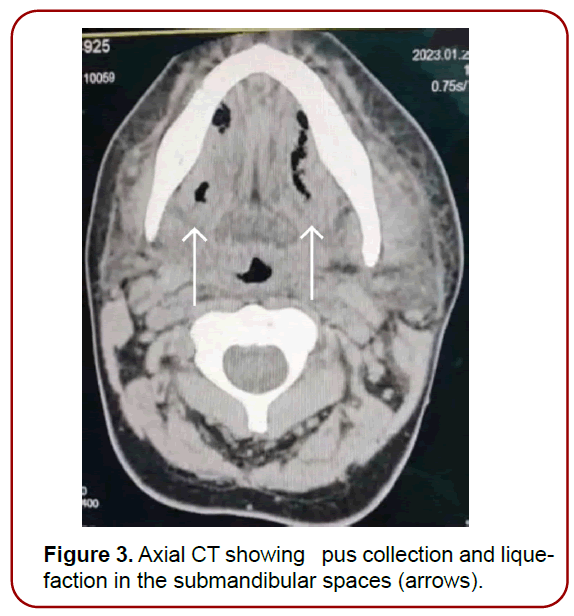

Complete blood picture showed leukocytosis. Computed tomography of the neck showed air foci in the submental, bilateral submandibular and anterior visceral neck spaces (Figure 2-4). Flexible fiberoptic assessment of the upper airway showed laryngeal edema.

Figure 3. Axial CT showing pus collection and liquefaction in the submandibular spaces (arrows).